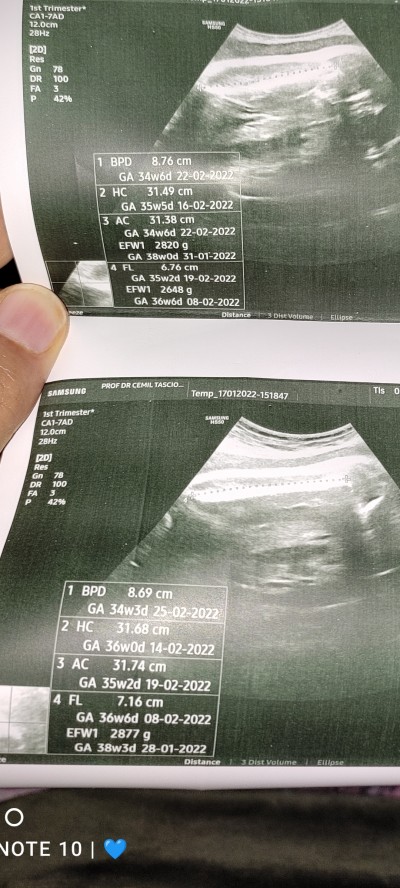

Kızlar USG den anlayan var mı.38 haftalık hamileyim. Haftaya sezeryan dedi doktor ama önce perinatoloji görsün dedi. Biraz zayıf falan dedi. Ciğerleri gelişmiş ama kuveze alabiliriz diyo. Çok canım sıkkın lütfen yardımcı olur musunuz

image

Gebelik haftası 38

Canım üzmek istemem ama kilosu iyi görünüyor diğer ölçümler haftasına göre geride o yüzden yönlendirmiş seni